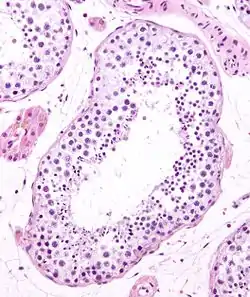

Seminiferous tubules are located within the testicles, and are the specific location of meiosis, and the subsequent creation of male gametes, namely spermatozoa.

The epithelium of the tubule consists of a type of sustentacular cells known as Sertoli cells, which are tall, columnar type cells that line the tubule.

In between the Sertoli cells are spermatogenic cells, which differentiate through meiosis to sperm cells. Sertoli cells function to nourish the developing sperm cells. They secrete androgen-binding protein, a binding protein which increases the concentration of testosterone.

Seminiferous tubule (transverse section).